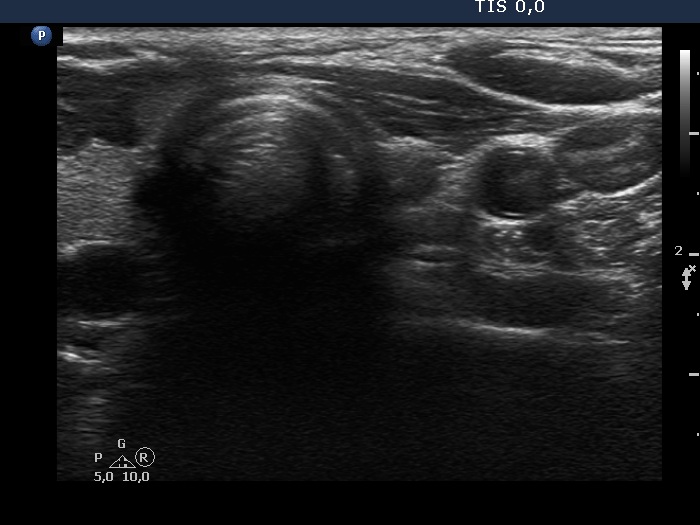

Second examination a year later (second row of images)

Clinical data: The patient had no complaints except for COVID-19 infection 3 months before the present visit.

Palpation: unchanged.

Hormonal investigation: TSH 3.10 mIU/L.

Ultrasonography revealed that the discrete hypoechoic lesion in the left lobe had increased in size, the dimensions were 4x4x5 mm, width, depth and length, respectively. There was a lymph node lateral to the left lobe. The node presented a heterogeneous pattern and lacked a regular hilum.Suggestion: repeat ultrasound in 3 to 6 months.